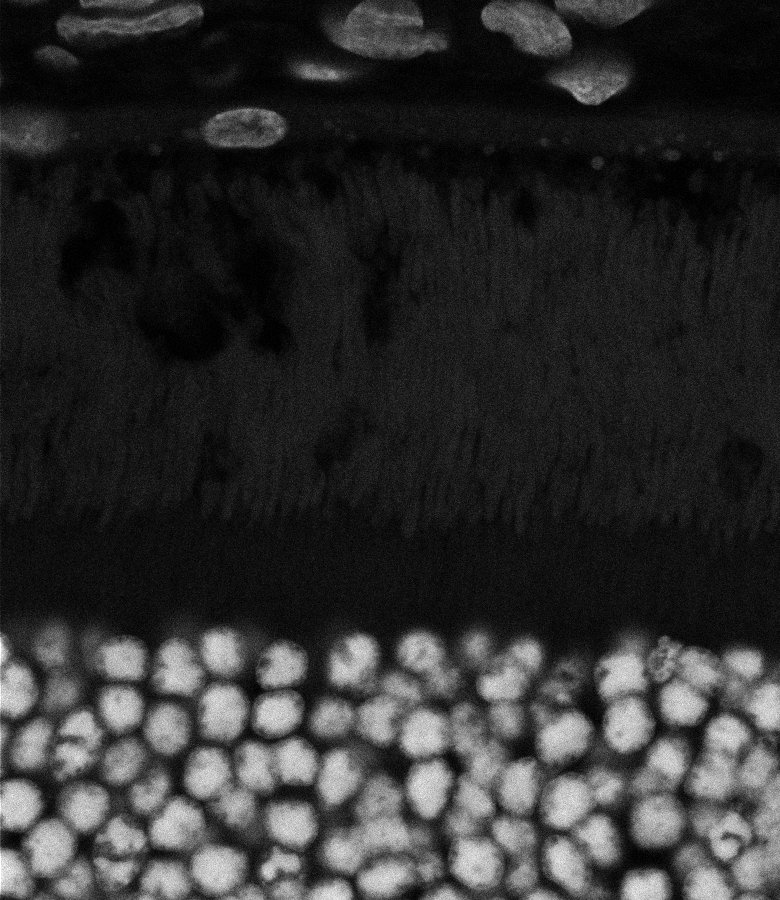

Healthy Retina

Unhealthy Retina